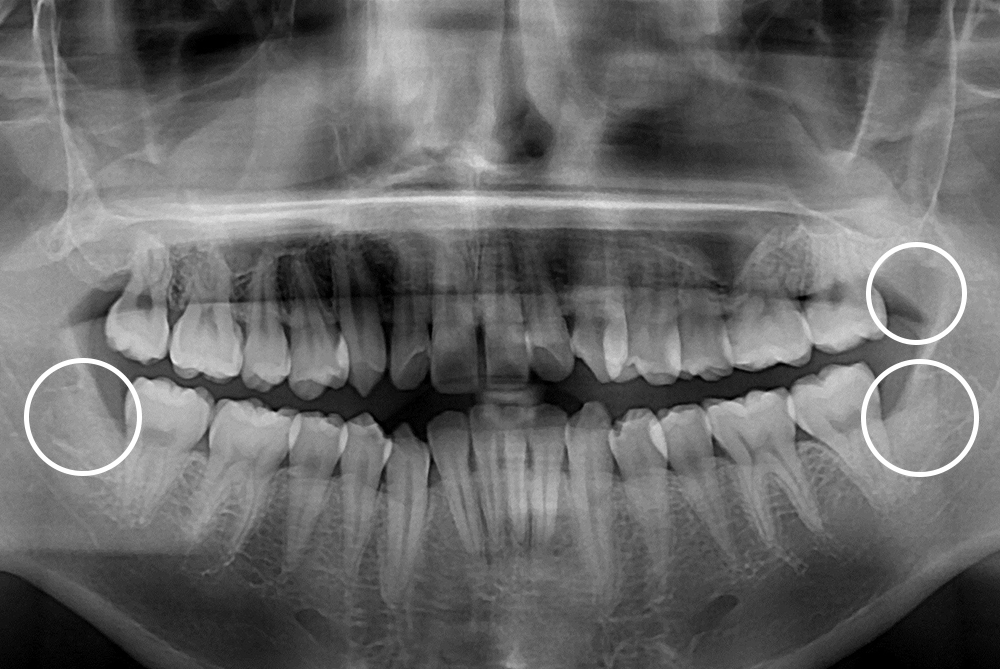

[사랑니] 매복 사랑니 발치

치료전 : 2018-11-30